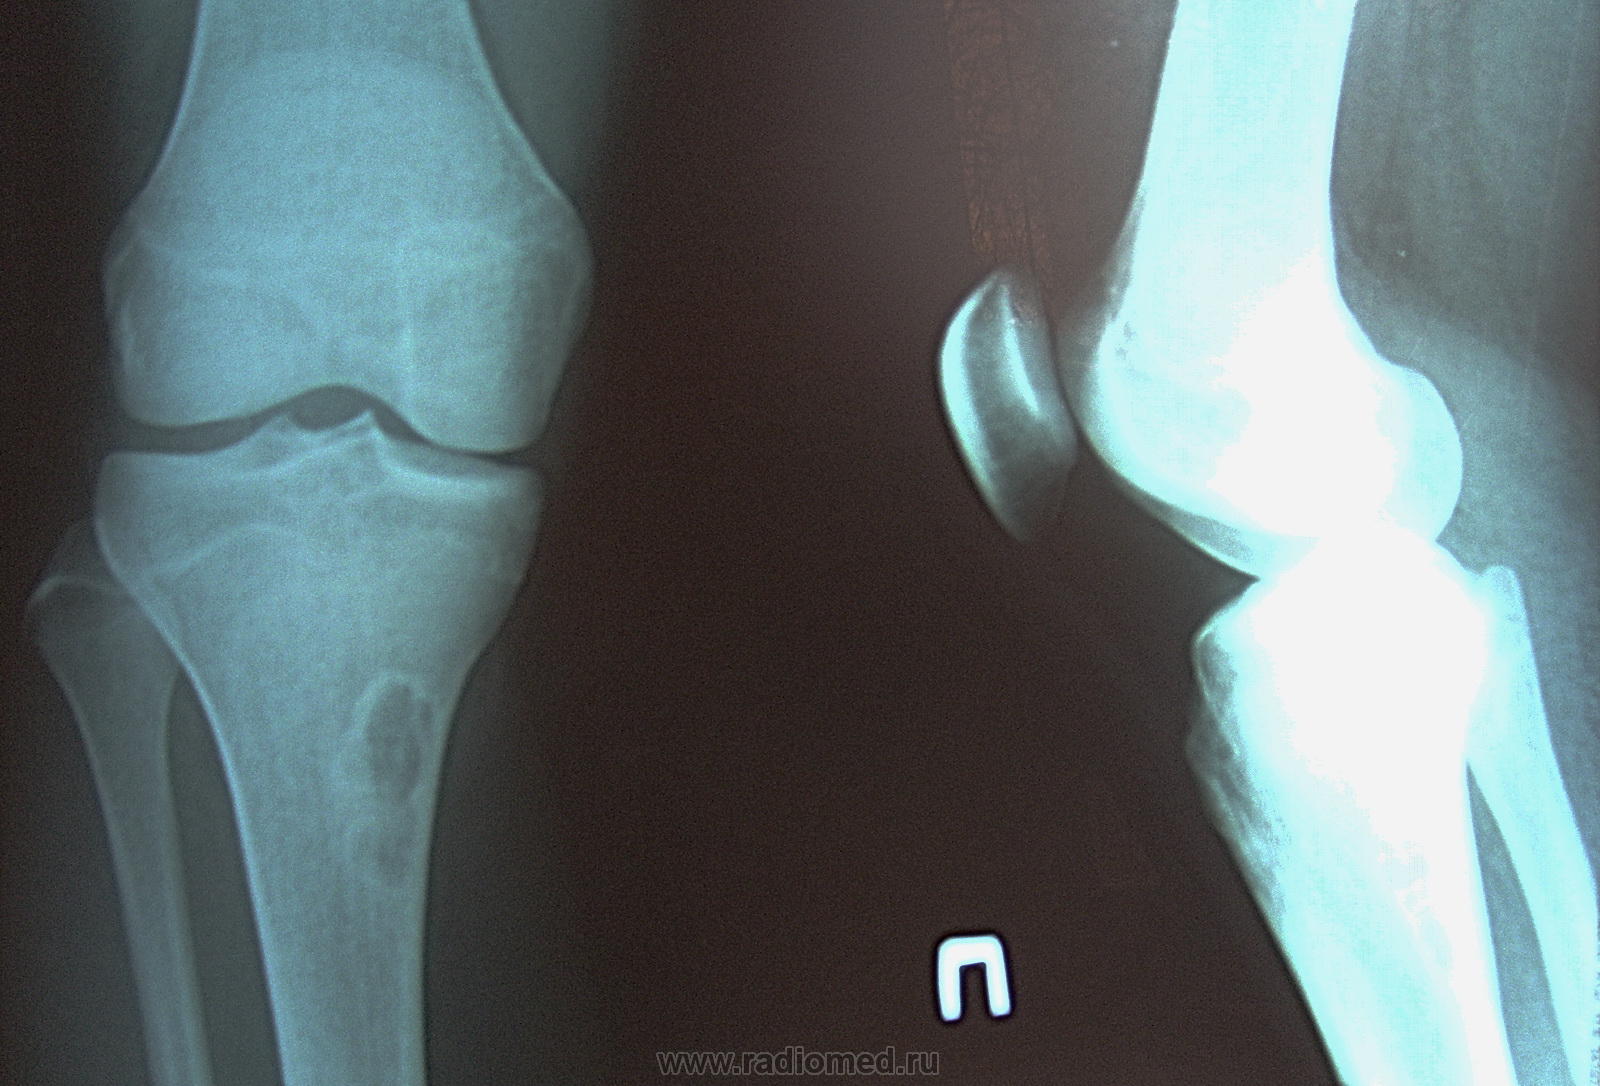

пришла в кабинет после травматолога. Занимается футболом. Была травма и после этого, около месяца назад почувствовала боли в этом коленном суставе. Честно говоря на ум конкретного ничего не пришло кроме остеомиелта. остеохондропатии и туберкулёза. Какие будут ещё мнения уважаемые коллеги?

неоссифицирующая фиброма (син. метафизарный кортикальный дефект)

Может быть многие не согласятся со мной, но точно такой же снимок я видела , когда ещё училась в интернатуре. Молодой человек усердно занимался упражнением "пистолет", клиника и локализация такие же, как в данном случае. После устранения физической нагрузки, снимки повторили через некоторое время (какое- не знаю), на Р-граммах- норма. Т.о. сделали вывод, что это зоны функциональной перестройки.

угу, метафизарные кортикальные дефекты относят к Лоозеровским зонам